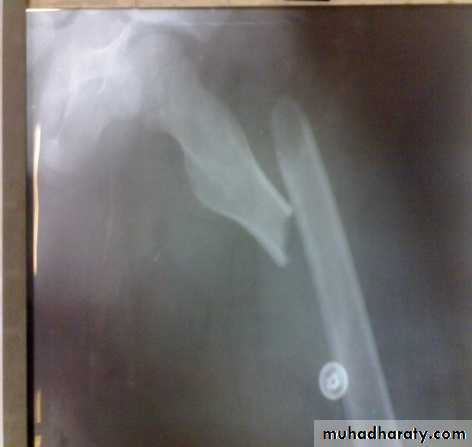

Open reduction and plating

Out of favor because of high rate of complications e.g. implant failure, infection…Indications:

Shaft and neck fractures.

Vascular injury.

Implant failure

Intramedullary nail with interlocking screws is the method of choice